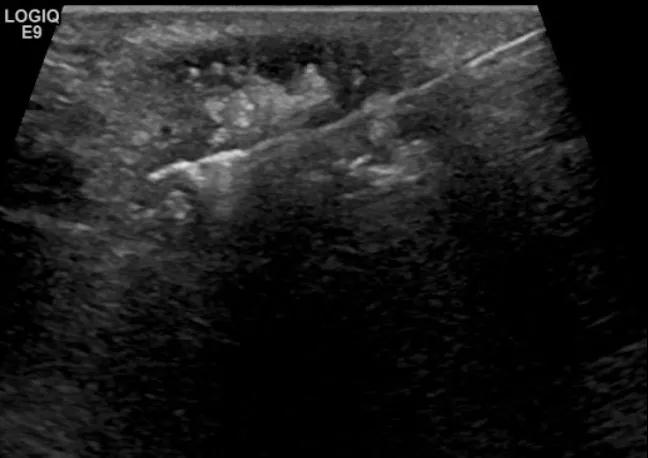

第二例是食管癌患者,术后半年余锁骨上固定淋巴结可触及肿大,疼痛非常明显,系统治疗后无缓解,患者希望通过局部处理缓解症状。造影显示强化信号明显,结节部分区域坏死,故主要针对强化区域从后向前的逐层的消融,皮下进行液体隔离减少烫伤。热消融后影像显示血流增强消失,弹性、硬度增高,一个月后复查显示充盈缺损,完全消融,疗效远超预期。

(病例2图例)